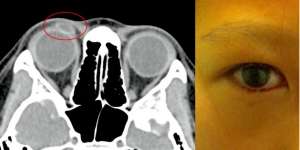

Dikira Bintit dan Berdarah, Mata Bocah Itu Ternyata...

Minggu, 1 Mei 2016 08:01

Lensa kontak telah mendekam di mata kanan anak itu selama dua tahun.